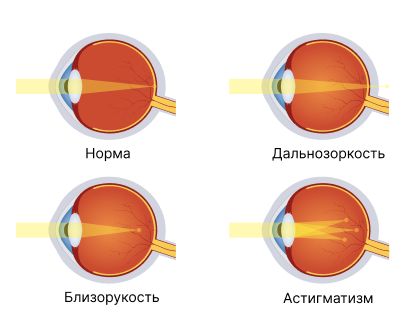

- близорукость и дальнозоркость с астигматизмом или неправильной коррекцией;

Аномалии рефракции глаза

Аномалии рефракции (близорукость и дальнозоркость, осложнённые астигматизмом) обычно вызывают монокулярную диплопию. Это происходит из-за неправильного преломления света и отсутствия единой точки фокуса на сетчатке, что приводит к нечёткости контура. Такой же эффект возникает при неадекватной коррекции этих аномалий: некорректные очки или контактные линзы искажают изображения, соответственно появляется нечёткость и размытость.